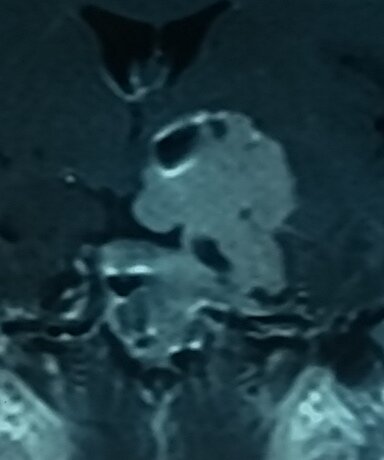

Пролактинома с экстраселлярным распространением